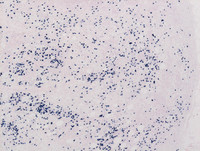

Figure 4: Breast lump-IgG4

Low power (Image to the left) and high power (Image to the right) photomicrographs showing increased IgG4 positive plasma cells, which are often seen in RDD but does not mandate designation as IgG4 related disease.